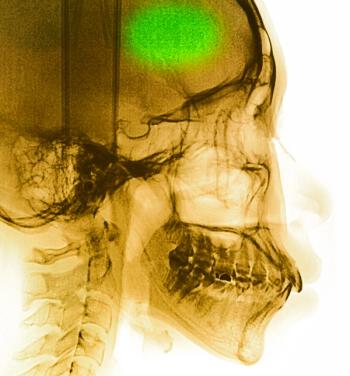

Results of a recent study suggest the presence or absence of CMBs may help refine risk prognostication in patients with AF.